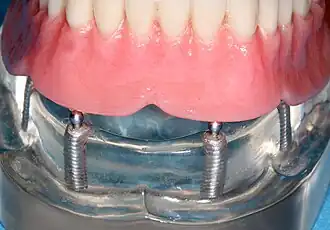

A maxillary overdenture may be supported by implants.[5] Even though there is no solid evidence to prove how many implants would be ideal to stabilise an overdenture, the most common number of implants used to stabilise a maxillary denture is 4.[5]

Implant-supported

Edentulous patients with sufficient amount of bony ridge on their jaws can opt for implant supported overdenture.[4] This type of over denture gains support from both the dental implants and intraoral tissues. Having implant-supported overdenture provides better stability of prosthesis and reduce bone resorption.[9] However, a conventional complete denture can be considered as an alternative due to less treatment time needed.[10]